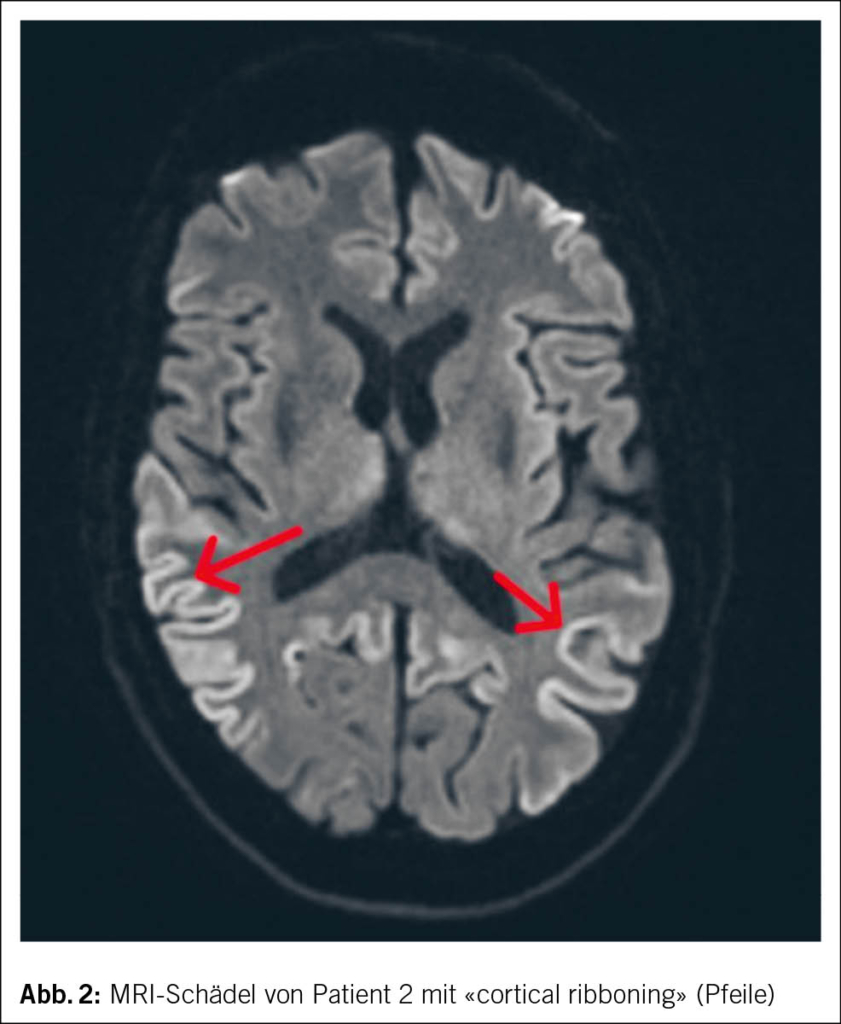

Im MRI des Schädels des zweiten Patienten zeigten sich streng kortikale, hyperintense Signalveränderungen ohne Einbezug der subkortikalen weissen Substanz, ein sogenanntes «cortical ribboning» (Abb. 2). Im Liquor wurden ebenfalls eine positive RT-QuIC für Prionen und ein positives Protein 14-3-3 festgestellt. Hinweise für eine infektiöse oder entzündliche Ursache fanden sich nicht.

Bei charakteristischer Klinik mit rasch progredientem Verlauf und den typischen Befunden im MRI des Schädels sowie in Liquor und EEG lag bei beiden Patienten das Bild einer sCJD vor. Bei Patient 2 wurde die Diagnose post mortem in der Histopathologie des Hirngewebes gesichert (Abb. 3).

Bei den meisten Patienten sind der zerebrale Kortex und die Basalganglien involviert. Typisch ist ein sogenanntes «cortical ribboning» (2, 6), also kortikale Signalalterationen in den Sequenzen der «fluid attenuated inversion recovery» (FLAIR) sowie in den diffusionsgewichteten Aufnahmen («diffusion weighted imaging», DWI) (13).